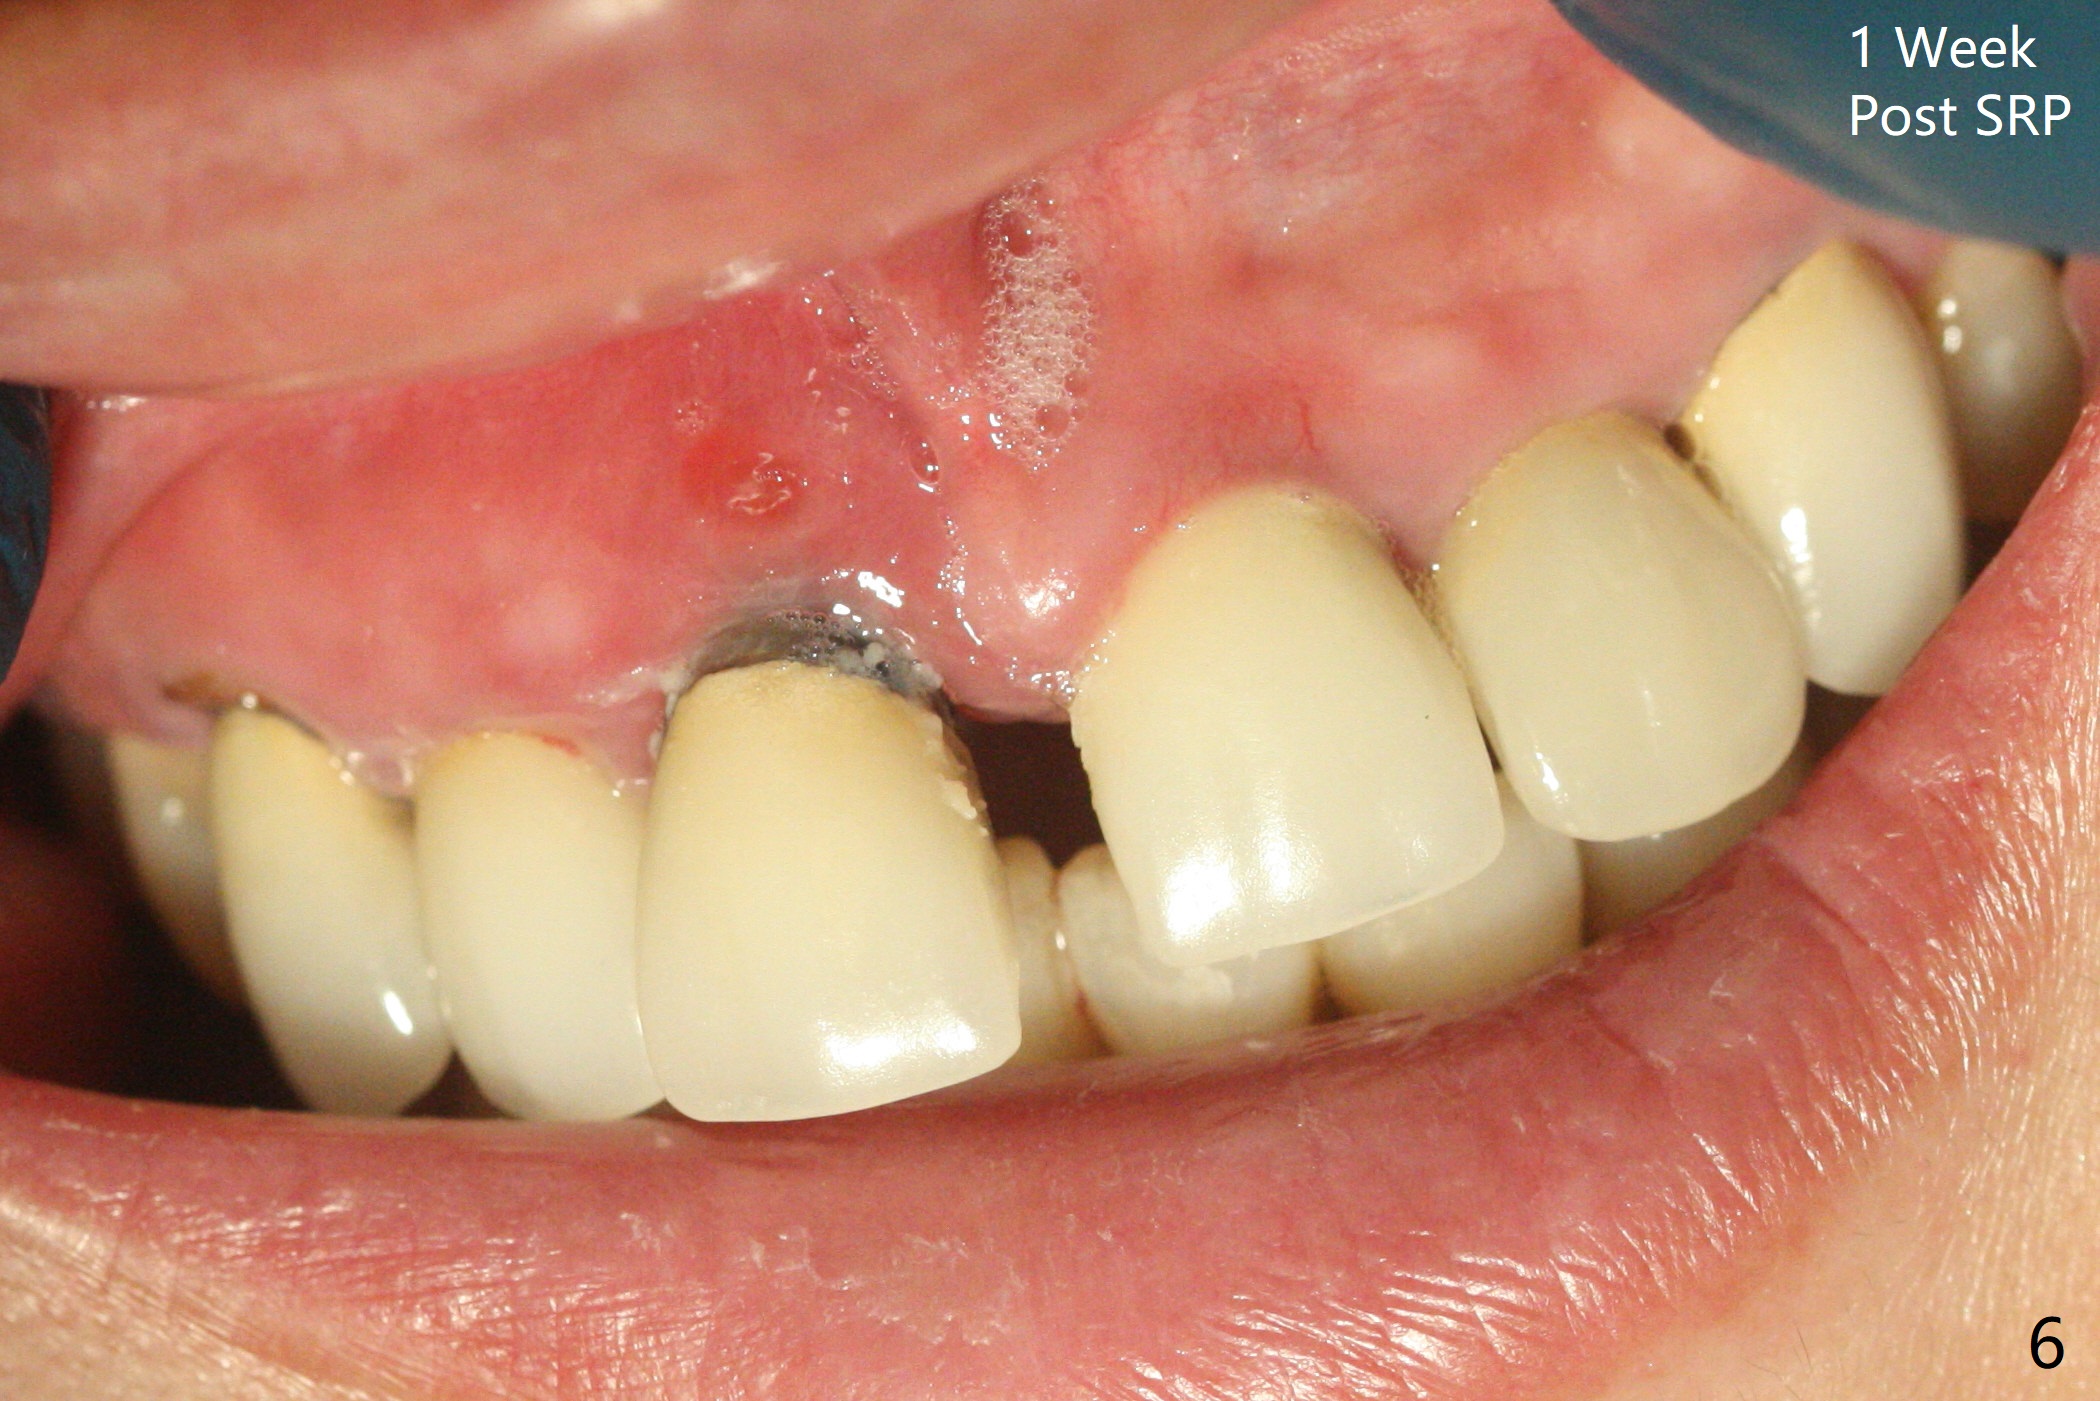

45岁女,害怕治疗,5年多没就医,右上1移位(图一(*),二),严重骨吸收(图三)。深洗后,即刻种植,由于牙龈7毫米长(图四,五)和使用粘性骨粉(骨壁再生),植体可以植浅些(图四:箭头)。上颌深洗一周后,除了患牙,牙龈红肿消除很多(图六,七)。